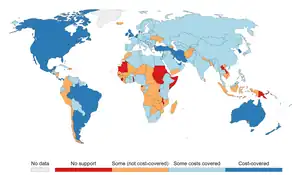

Several countries have taken measures to control the consumption of tobacco (smoking) with usage and sales restrictions as well as warning messages printed on packaging. Additionally, smoke-free laws that ban smoking in public places such as workplaces, theaters, and bars and restaurants have been enacted to reduce exposure to second-hand smoke.[3] Tobacco taxes that increase the price of tobacco products have also been enacted.[3]